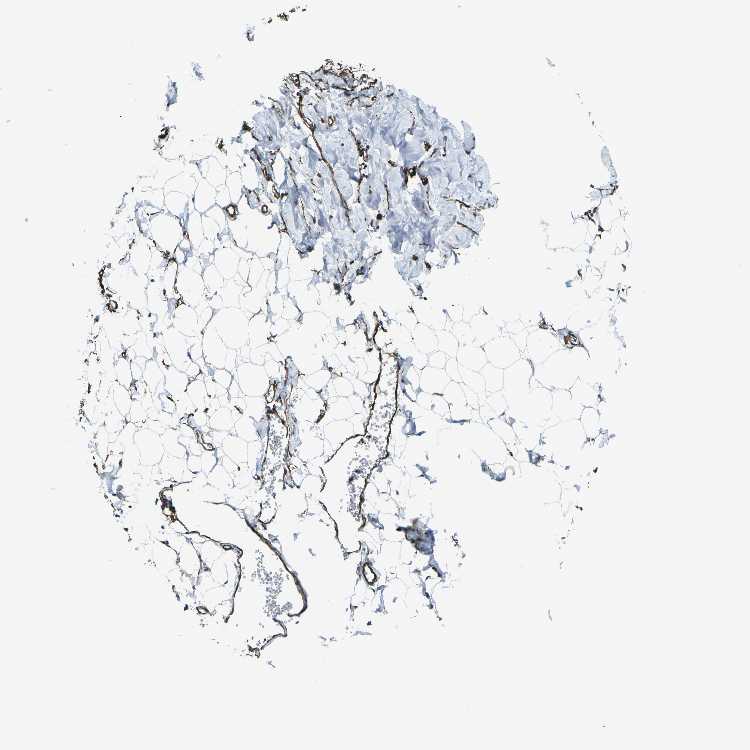

BREAST - Antibody stainingi

Antibody staining in the annotated cell types in the current human tissue is reported as not detected, low, medium, or high, based on conventional immunohistochemistry profiling in selected tissues. This score is based on the combination of the staining intensity and fraction of stained cells.

Each image is clickable and will lead to virtual microscopy that enables deeper exploration of all samples and also displays staining intensity scores, fraction scores and subcellular localization as well as patient and tissue information for each sample.

Antibody HPA012316

Adipocytes Not detected

Glandular cells Medium

Myoepithelial cells High